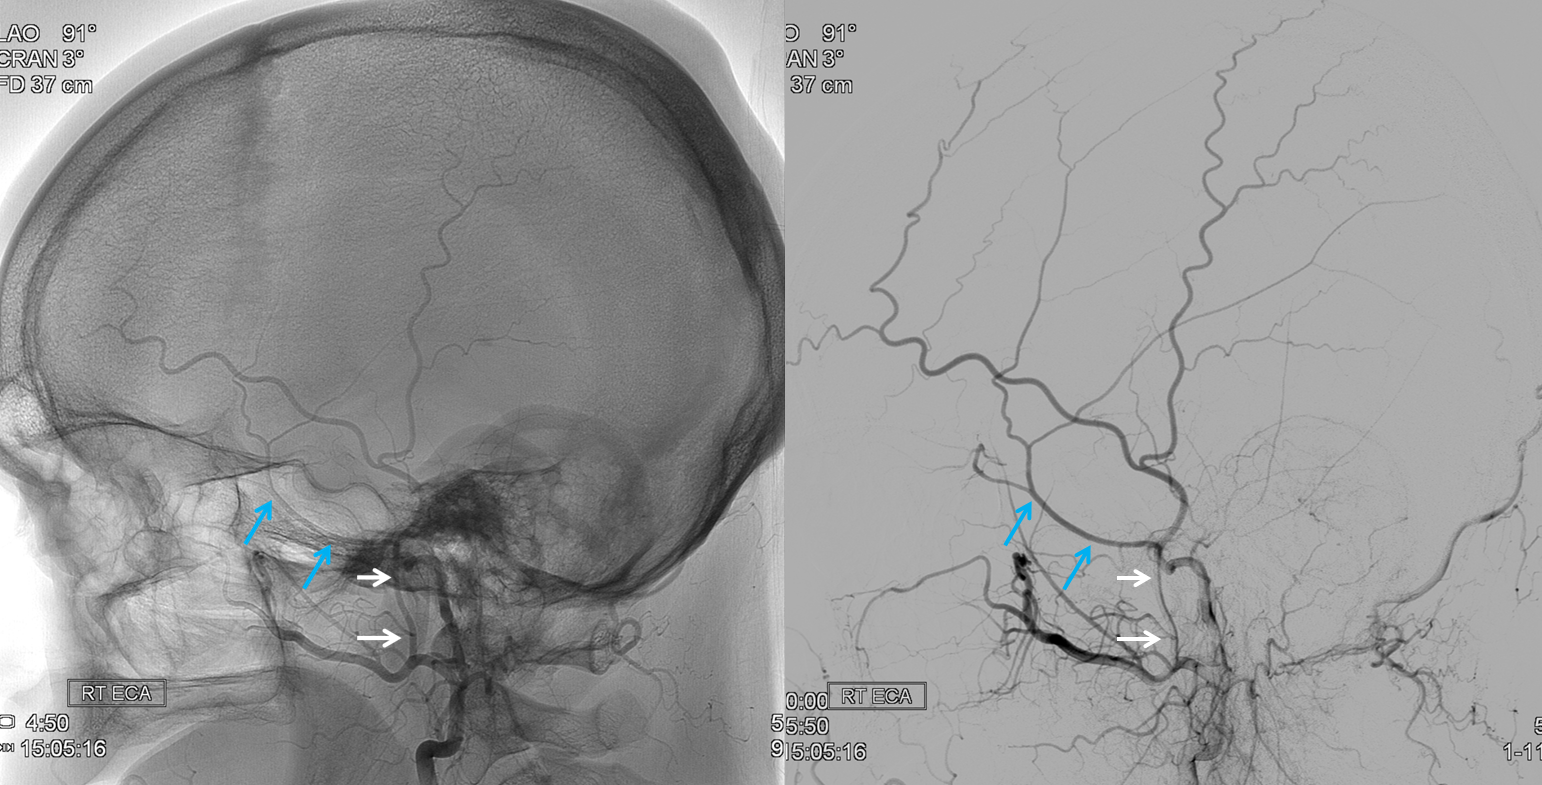

Below is a case of severe venous sinus thrombosis and secondary parenchymal venous infarcts

The explanation for the above tragic pattern is below. On the right, sigmoid and transverse sinuses are patent. However, the Labbe is hypoplastic, and majority of outflow used to go to the Trolard, into the now occluded SSS. There is no other effective way to go — the trolard tries to decompress via a left diploic vein, and convexity tries to access the deep venous system (which normally should not be well-seen in setting of hypoplastic right A1 segment). The left situation is much better, as well-developed superficial sylvian veins drain into the patent Cavernous Sinus. Thus, despite thrombosis of the left transverse and sigmoid sinuses, the left hemisphere is doing better, while the right one, which has patent transverse and sigmoid sinuses, is devastated.

Post venous thrombectomy — with limited results. Note presence of same left diploic vein as seen in right ICA injection, and connection between the distal superior sagittal sinus and the deep venous system via the inferior sagittal sinus.